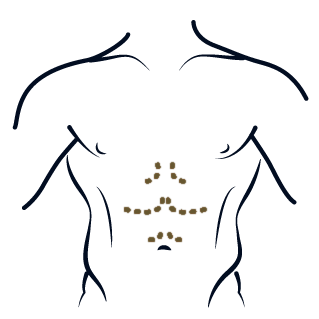

Six Pack

CIRUGÍA CORPORAL

Liposucción de alta definición de la pared abdominal, con vaser lipo.

VASER, LIPOESCULTURA de Alta Definición

CIRUGÍA CORPORAL

Extraer la grasa subcutánea tramite una cánula con el fin de esculpir el contorno